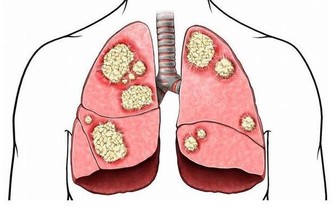

人為什麼會做春夢、被鬼壓床? 這8 種夢或是疾病信號

當然,必須強調的是,這張圖目前主要是根據醫生經驗判斷得出的,疾病導致了某某夢境,僅僅是有可能性,並不一定準確。

覺得自己身體不舒服,最好的辦法還是親自去醫院看醫生,做檢查,得到確切的診療。